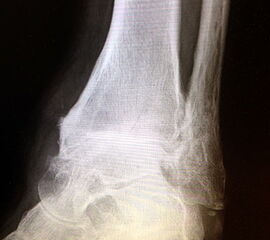

Erreichen eines schmerzfreien oberen Sprunggelenkes mit belastbarem und plantigrad aufsetzbarem Fuss (Abb. 1a und b) unter Verzicht auf die Bewegungsfunktion des oberen Sprunggelenkes. Operative Resektion der arthrotisch veränderten Gelenkflächen bis in den subchondralen frischen Knochen von Tibia und Talus. Fusion mittels Kompressionsschrauben oder Arthrodeseplatten, bedarfsweise Arthrodesenagel.

Abbildung 1a

Abbildung 1b